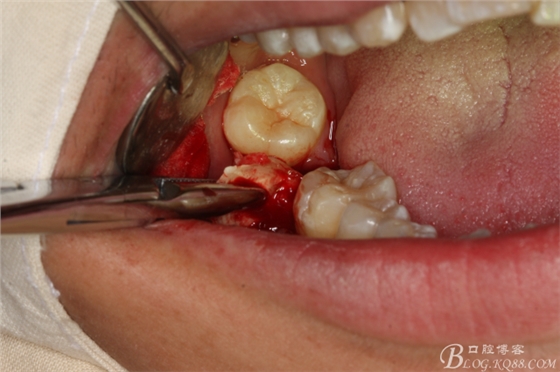

圖20.金剛砂車針片切44牙冠、消除鄰牙阻力

圖21.片切完成的44牙冠

圖22.微創(chuàng)挺增間隙

圖23.放置牙鉗拔除

圖24.拔除44